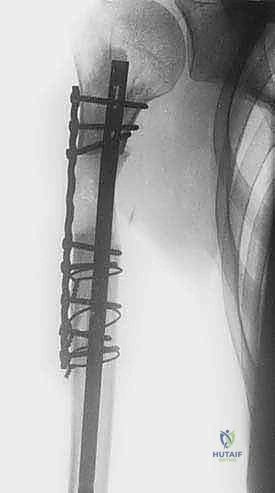

* المسمار النخاعي التشابكي (Intramedullary Nailing): يتم إدخال سيخ معدني قوي من التيتانيوم داخل التجويف النخاعي لعظم العضد بالكامل، وتثبيته بمسامير عرضية من الأعلى والأسفل. هذه الطريقة توفر دعماً ميكانيكياً هائلاً للعظم، وتمنع الكسر، وتسمح للمريض باستخدام ذراعه فوراً.

* غالباً ما يتم إجراء هذه الجراحة بتدخل محدود (Minimally Invasive) باستخدام أجهزة التنظير الإشعاعي (C-arm) داخل غرفة العمليات لضمان الدقة المطلوبة دون الحاجة لشق جراحي كبير.

إعادة البناء الميكانيكي: يتم إدخال المكونات المعدنية (سواء مسمار نخاعي، شرائح، أو مفصل صناعي) وتثبيتها بقوة باستخدام الإسمنت العظمي إذا لزم الأمر. يتم التأكد من ثبات الهيكل الجديد تحت جهاز الأشعة السينية المباشر (C-arm).